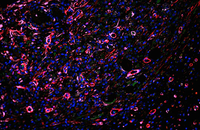

- Confirmation of the nature of differentiated cells by ICC method

- Investigation of cell placement on tissue scaffold